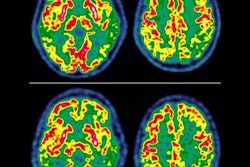

For image interpretation, the researchers started with either MRI, DWI-MRI, or PET alone. They then explored the usefulness of different combinations of these approaches: MRI plus DWI or MRI plus PET, and then finally an approach that included all three modalities together (MRI plus DWI and PET). The accuracy, sensitivity, and specificity were determined for each method.

According to the results, with MRI as a reference (with a sensitivity of 100% and a specificity of 74%), the addition of the PET qualitative metric increased MRI specificity to 80% for downgrading BI-RADS category 4 lesions in patients, Romeo noted. When considering an approach using all three modalities together, the sensitivity was 100% and the specificity remained quite high at 80%, she added.